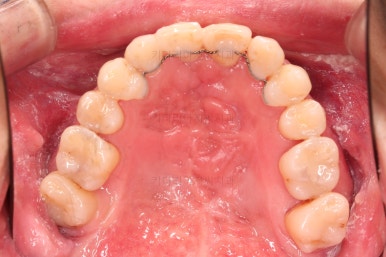

1. 초진 시 입안의 모습

부산구순구개열교정 키다리아저씨치과에 처음 내원하셨을 당시의 입안의 모습입니다.

이번 환자분도 이와 같은 일반적인 특징이 그대로 나타나 있었습니다.

양측성 구순구개열이었으므로 작은 앞니(대문니와 송곳니 사이)가 양쪽 다 결손이었고, 또 다른 이유로 아래 앞니도 1개 없는 상태였습니다.

✅ 악궁확장도 하지 않기로 했습니다.

앞서 입안의 모습에서 위턱뼈의 가로폭이 좁다라는 말씀을 드렸는데요.

잇몸의 베이스가 되는 골격 자체가 좁은 경우

어금니쪽은 괜찮은데, 앞쪽으로 올수록 골격이 좁아지는 경우

베이스가 되는 골격은 괜찮으나 치열이 안쪽으로 쏠려 있어서 좁게 평가된 경우

세 경우 각각 사용하는 장치가 모두 다르며, 이번 환자분은 3번에 가까웠습니다.

어쨌든 이번 환자분은 적극적인 악궁확장 장치까지는 필요 없었고, 브라켓-와이어로만 부산구순구개열교정으로 개선해 보기로 했습니다.